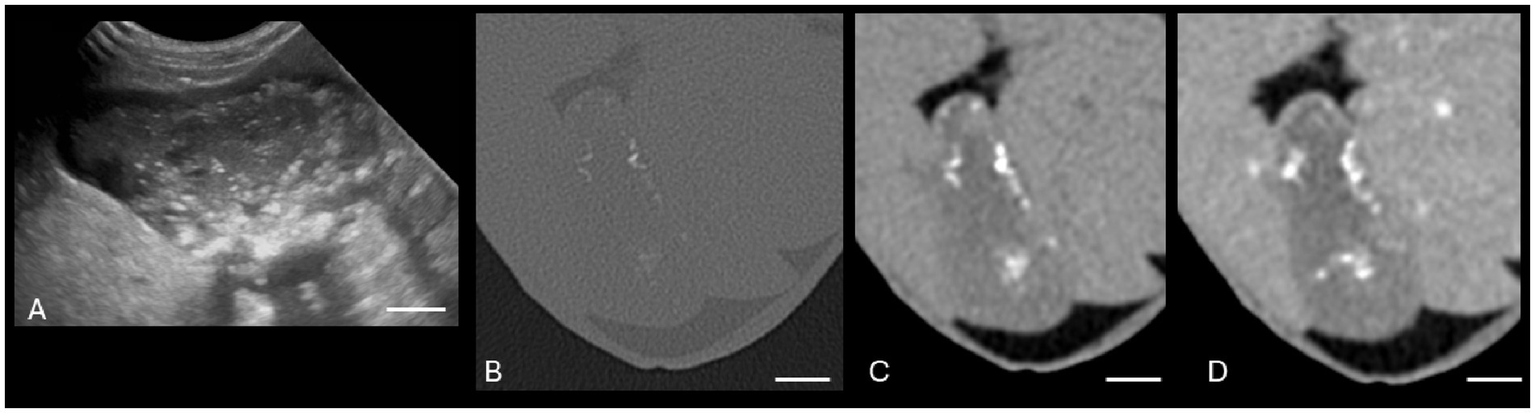

There were various degrees of agreement between US and CT for the following conditions: gallbladder wall edema (moderate agreement), cholecystitis (good agreement), and CMH (poor agreement). Specific ICCs are provided in Table 2. Both US and CT successfully identified the two gallbladder wall edema cases. In addition, CT had three false positives for gallbladder wall edema. Both US and CT successfully identified the 21 cholecystitis cases based on symmetric or asymmetric gallbladder wall thickening, double-layered gallbladder wall, and hypoechoic gallbladder wall (14, 15). Many of these cases had concurrent pathologies such as a gallbladder mucocele and cholelithiasis. Ultrasound only successfully identified five of the 13 cases with cholelithiasis (Figure 3). Computed tomography identified all the cases of cholelithiasis with one additional false positive (a case with a histopathologically confirmed gallbladder mucocele).

Figure 3. Canine cholelithiasis on CT and US. (A) Ultrasound image using compound imaging with color Doppler interrogation in the sagittal plane. This structure is hyperechoic and did not display a twinkle artifact during interrogation, so it was interpreted to be inspissated gallbladder sludge. The shadow along the cranial aspect of the structure was interpreted to be an edge shadow artifact. (B–D) Transverse bone window (B), soft tissue window precontrast (C), and soft tissue window post-contrast arterial phase (D) CT images of the same patient. There is a mineral attenuating structure in the gravity-dependent portion of the gallbladder with an HU of 287, consistent with a cholecystolith. The shape is similar between the two modalities. Non-contrast enhanced bone window (WW = 4,000, WL = 500). The white calibration bar at the bottom right of each panel delineates 1.0 cm.